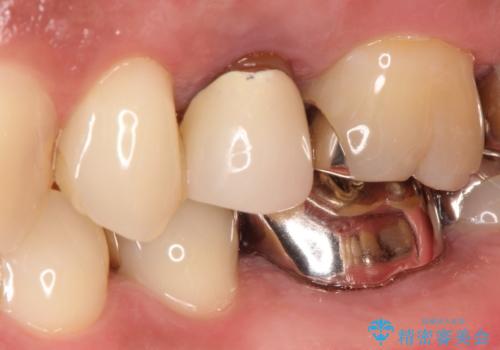

[根管治療・セラミック補綴] 歯ぐきを押すと痛い

![[根管治療・セラミック補綴] 歯ぐきを押すと痛いの症例 治療前](https://seimitsushinbi.jp/wp/wp-content/uploads/2020/06/af6939fea203eb3874487b1710bde0f0-500x350.jpg?v=1591340021)